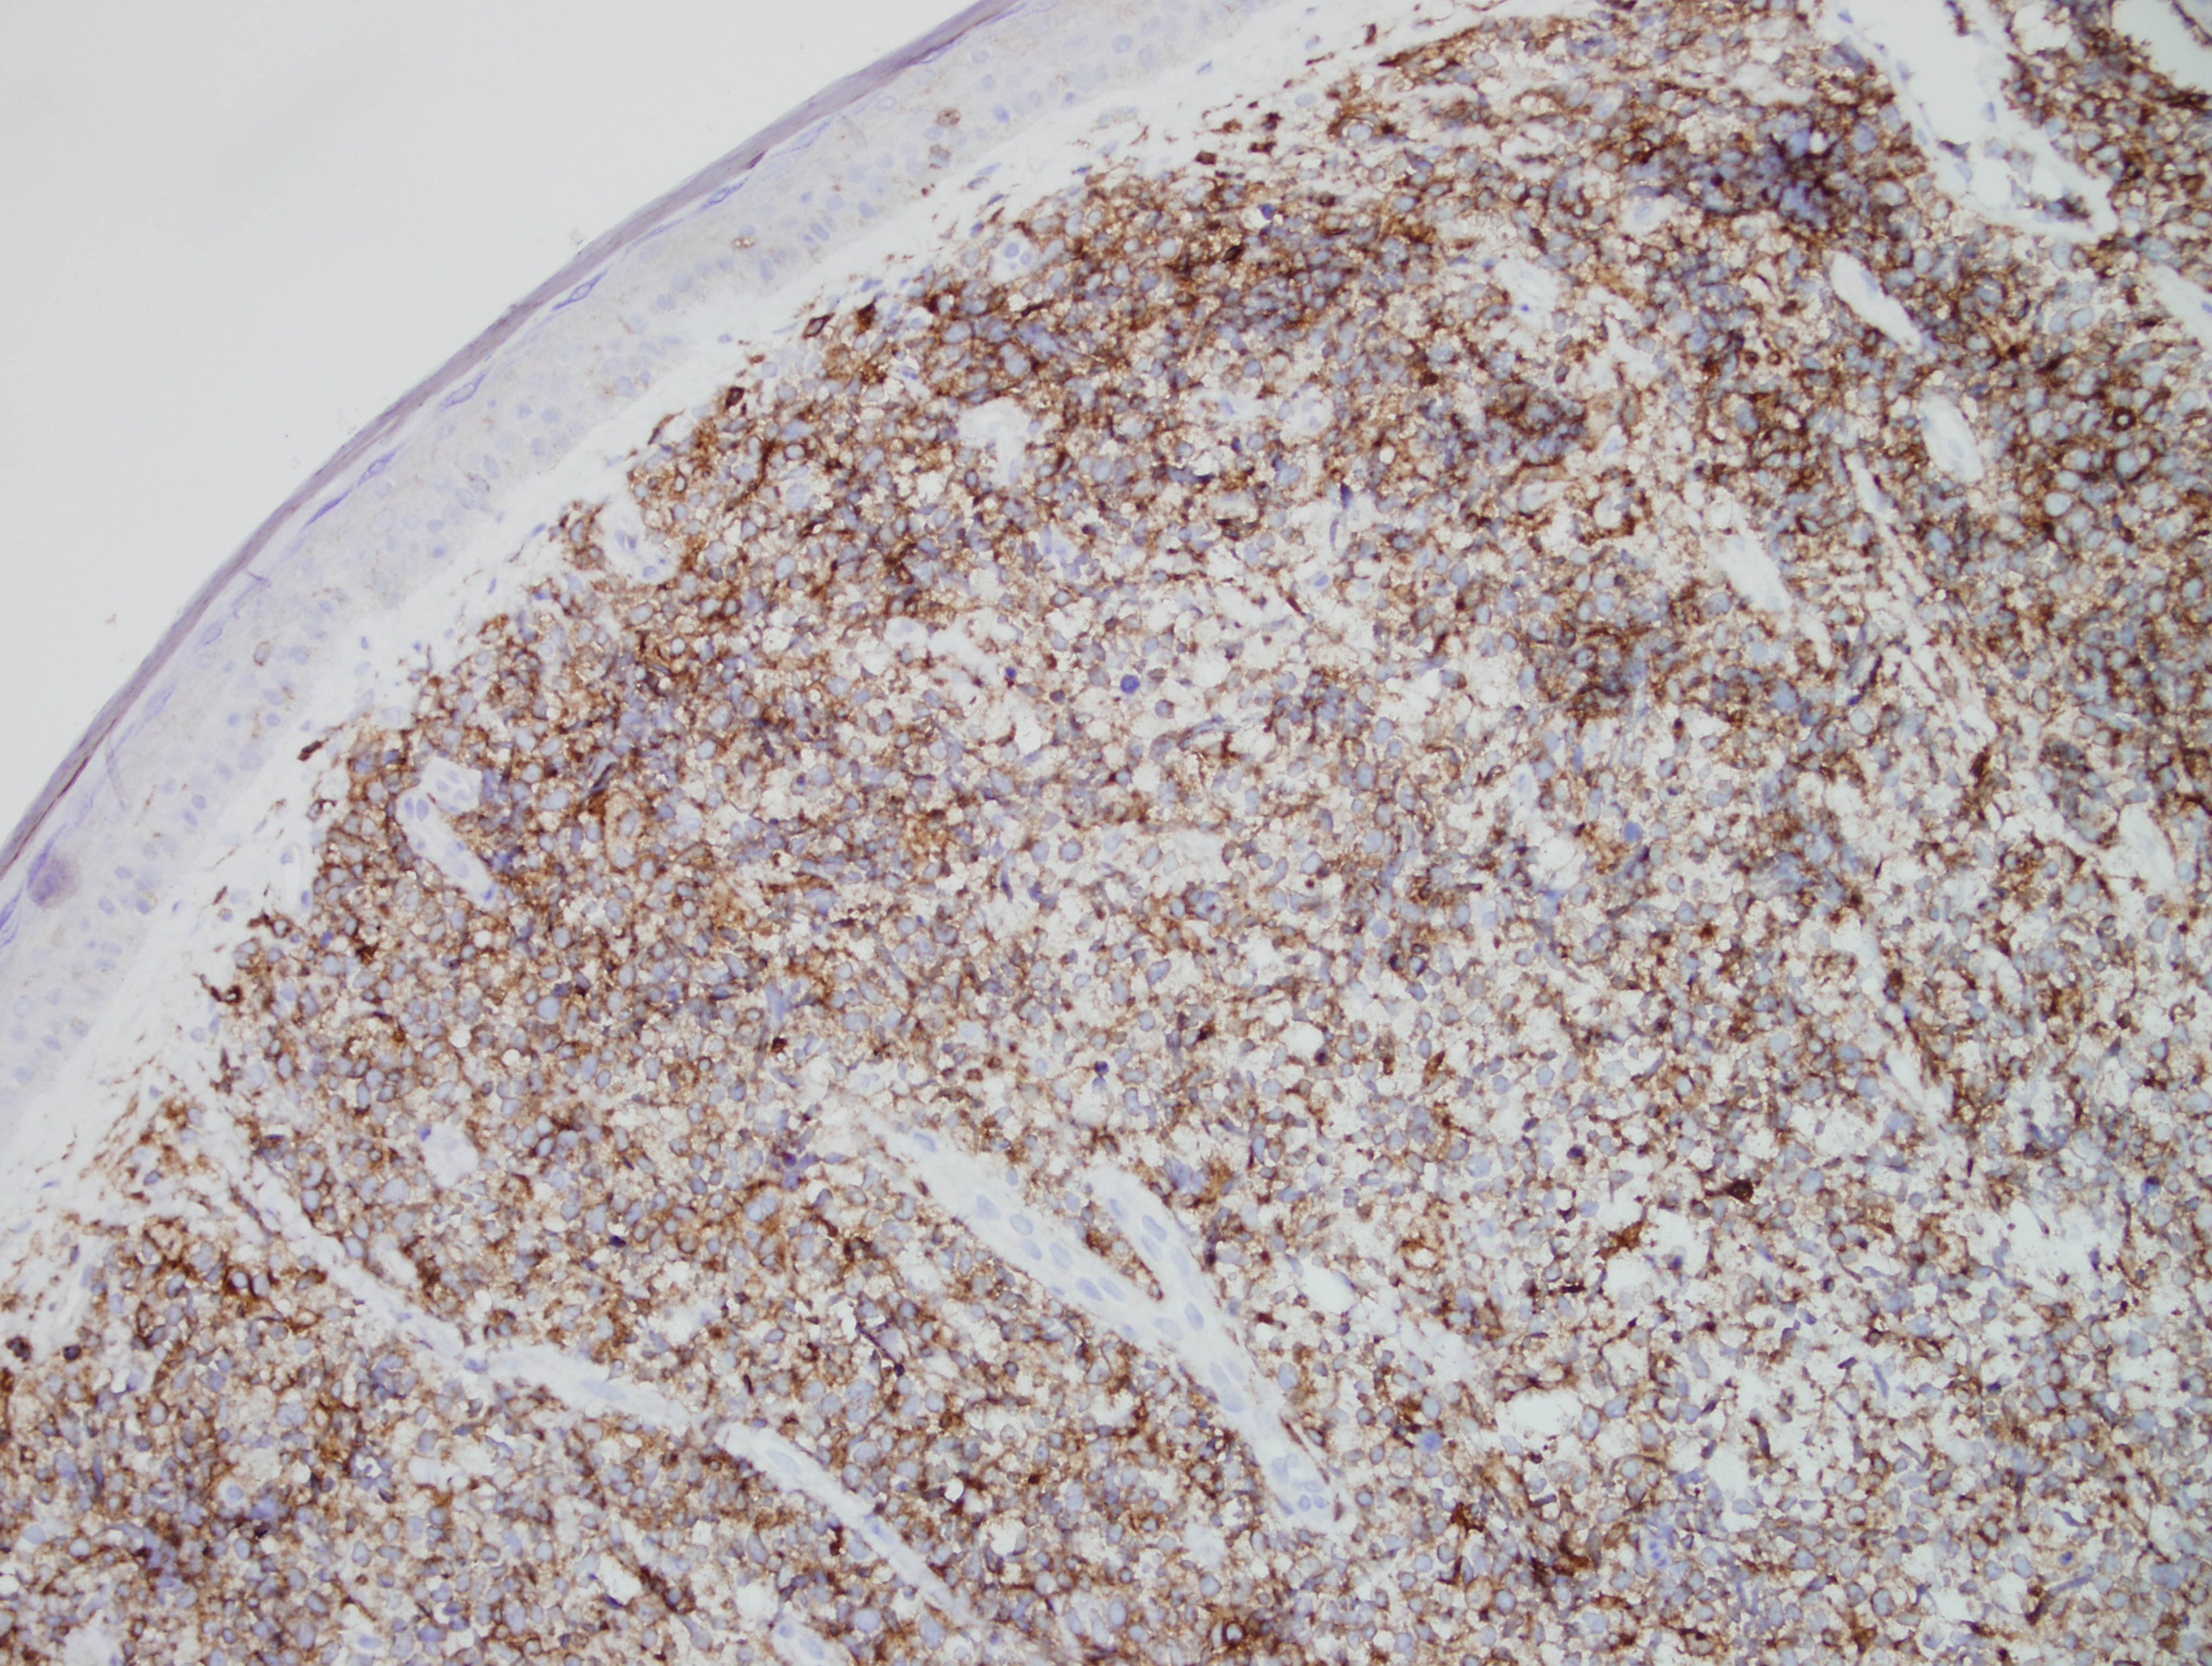

Morphologically, BPDCN is characterized by a diffuse infiltrate of blastoid, monomorphic and medium-sized cells with scant cytoplasm, irregular nuclei, fine chromatin, and nucleoli. Mitoses are typically present and necrosis is usually absent. With cutaneous manifestations, epidermotropism is not observed. Tumor cells typically express CD4, CD7+/-, CD56, CD123, CD303, TCL1, and CD43. Very rarely, CD56 can be negative. CD33, CD79a, BCL2, and BCL6 can also be expressed. T-cell and B-cell receptor genes are usually germline. Several recurrent chromosomal abnormalities have been noted, such as 5q21/5q34, 12p13, and 13q13-21.